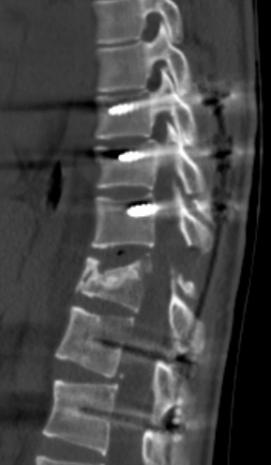

· T11椎体严重骨折变形

· 脊柱内固定跨越6个节段

CT提示脊髓脊柱严重损伤